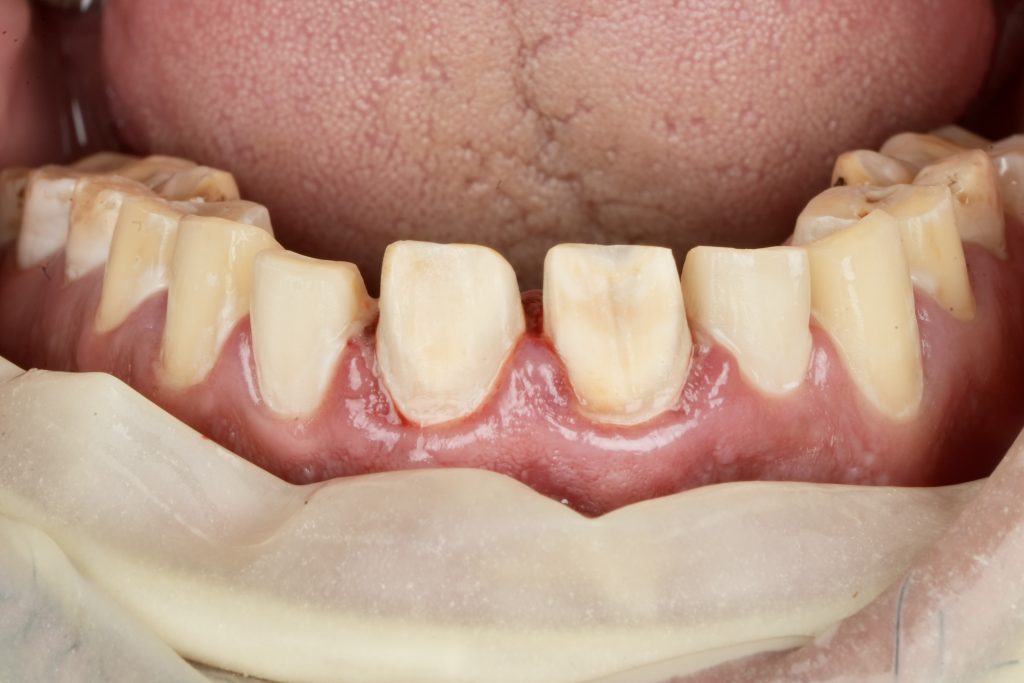

IPS E-max Press veneers were pressed and characterized using micro-layered incisal ceramics for vitality and translucency. Surface texture and internal effects were customized to simulate natural perikymata and halo zones (Fig 3).

Margins were refined using fine diamond strips, and surface gloss was enhanced with a multi-step polishing system (Shofu OneGloss + OptraPol Next Gen). Post-operative evaluation showed ideal incisal translucency, line-angle symmetry, and gingival health (Fig 5 & 6).